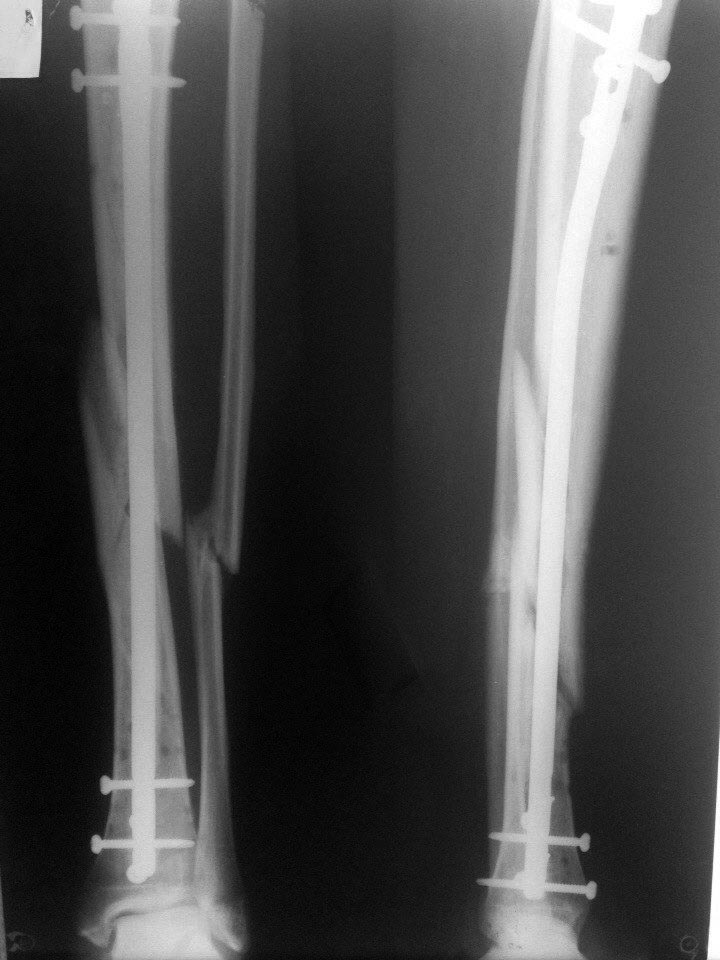

Ув. коллеги!Прошу Вашего совета. Пациент Н. 40 лет прооперирован 11 недель назад.

Закрытая репозиция, БИОС большеберцевой кости с рассверливанием. На повестке дня вопрос о дальнейшей тактике

Динамизировать нужно было через 6 - 8 нед после БИОС, но и сейчас не поздно - признаков консолидации нет.

Рентгенологических признаков сращения не видно, целесообразно удаление в проксимальном отделе гвоздя 3 статических винтов (зачем их так много?)

Я бы пожалуй оставил так и пусть ходит. Перелом репонирован неидеально, также есть большой центральный фрагмент. При динамизации будет эффект телескопа.

Проблема обусловлена невосстановленной длиной. Отсюда вальгус и незахлопнутая спираль. Динамизация... Может "срезаться" костная мозоль (если она есть), здесь же нет торцевого упора отломков.

Так что, наверно, либо ждать как есть, либо переделать с устранением всех недочетов. Пока есть подвижность, это нетрудно сделать, используя не раз обсуждавшийся дистрактор.